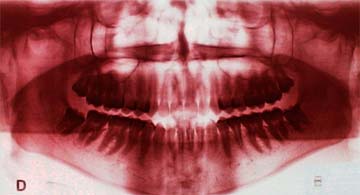

Razões e época do tratamento: Este tipo de má-oclusão deve ser tratada assim que diagnosticada por várias razões, entre elas, o fato da mordida cruzada posterior não se corrigir espontaneamente, de provocar desgaste anormal sobre as superfícies oclusais dos dentes, desenvolver problemas periodontais por trauma oclusal, provocar interferências no desenvolvimento e crescimento normais dos arcos dentários, além de que nos casos de mordidas cruzadas funcionais, que apresentam um desvio lateral da mandíbula pela presença de interferências oclusais, há uma alteração na posição dos côndilos. O côndilo do lado cruzado desvia-se para posterior e superior, enquanto que do lado normal desloca-se para anterior e inferior da fossa mandibular. Pode apresentar também alterações de atividade muscular acompanhada de maior intensidade unilateral(3). A não correção destes desvios em idade precoce pode acarretar uma assimetria estrutural facial na idade adulta, transformando-se em grandes deformidades. Além destes fatores, o tratamento precoce das mordidas cruzadas posteriores, resulta numa erupção adequada dos sucessores permanentes, melhora na relação esqueléticas das bases apicais e proporciona um padrão de fechamento bucal sem desvios. O momento para o tratamento da mordida cruzada posterior é tão logo seja diagnosticada esta má-oclusão(11), porém deve-se levar em conta a maturidade e possibilidade de cooperação da criança.

Para concluir este tema apresentaremos, como exemplo, um caso simples de mordida cruzada postural, desencadeada por respiração bucal em decorrência de uma rinite alérgica, a qual foi logo diagnosticada e convenientemente tratada. Observaremos também as prováveis implicações nas articulações temporomandibulares, estimuladas pelo uso do hiperbolóide com intuito de reprogramar o sistema estomatognático.